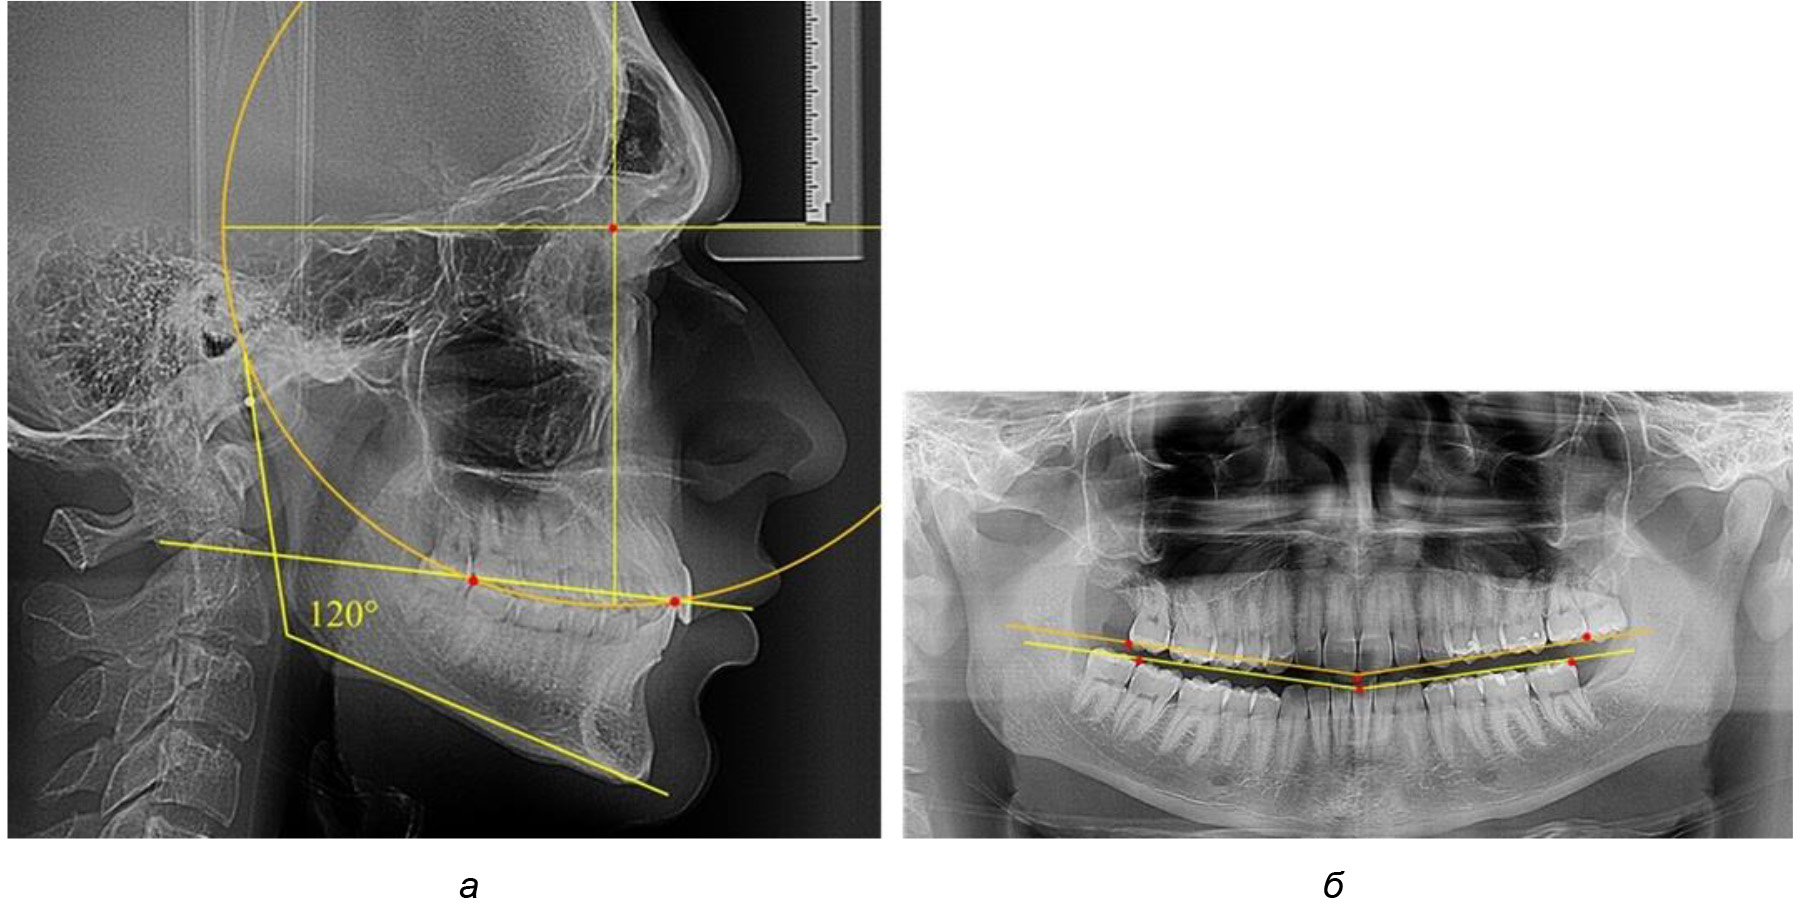

Рис. 2. Особенности кривой Spee на ТРГ (а) и ОПТГ (б) у людей с признаками вертикального роста

В ходе исследования установлено, что в 1-й подгруппу вошли ТРГ и ОПТГ 18 человек 1-й группы, что составило (29,03 ± 5,78) % от всех пациентов, рентгенограммы которых были проанализированы. У всех пациентов величина угла нижней челюсти была более 125° и в среднем составила (129,89 ± 3,62)° и характеризовала вертикальный тип нижней челюсти.

Учитывая существенную вариабельность линейных показателей, обусловленных типологическими (гнатическими и дентальными) вариантами зубочелюстных дуг, анализ проводили только при измерении глубины кривой Spee в наиболее углубленном месте и оценивали относительный показатель через отношение радиуса круга к сагиттальному расстоянию окклюзионной линии.

Анализ результатов показал, что глубина кривой Spee в среднем по подгруппе составил (4,12 ± 0,53) мм как при анализе ТРГ, так и ОПТГ.

Деление величины радиуса круга к длине окклюзионной линии составило 1,623 ± 0,02. Таким образом, для определения радиуса окружности, соответствующей кривизне окклюзионного контура боковой ТРГ, необходимо измерить расстояние между передней и задней окклюзионными точками и последующим умножением полученной величины на число Фибоначчи (рис. 2).